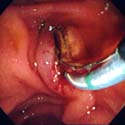

´ÙÀ½Àº ¿°Áõ¼ºÀåÁúȯÀÇ ´ëÇ¥ÀûÀÎ ´ëÀå³»½Ã°æ

¼Ò°ßÀÔ´Ï´Ù.